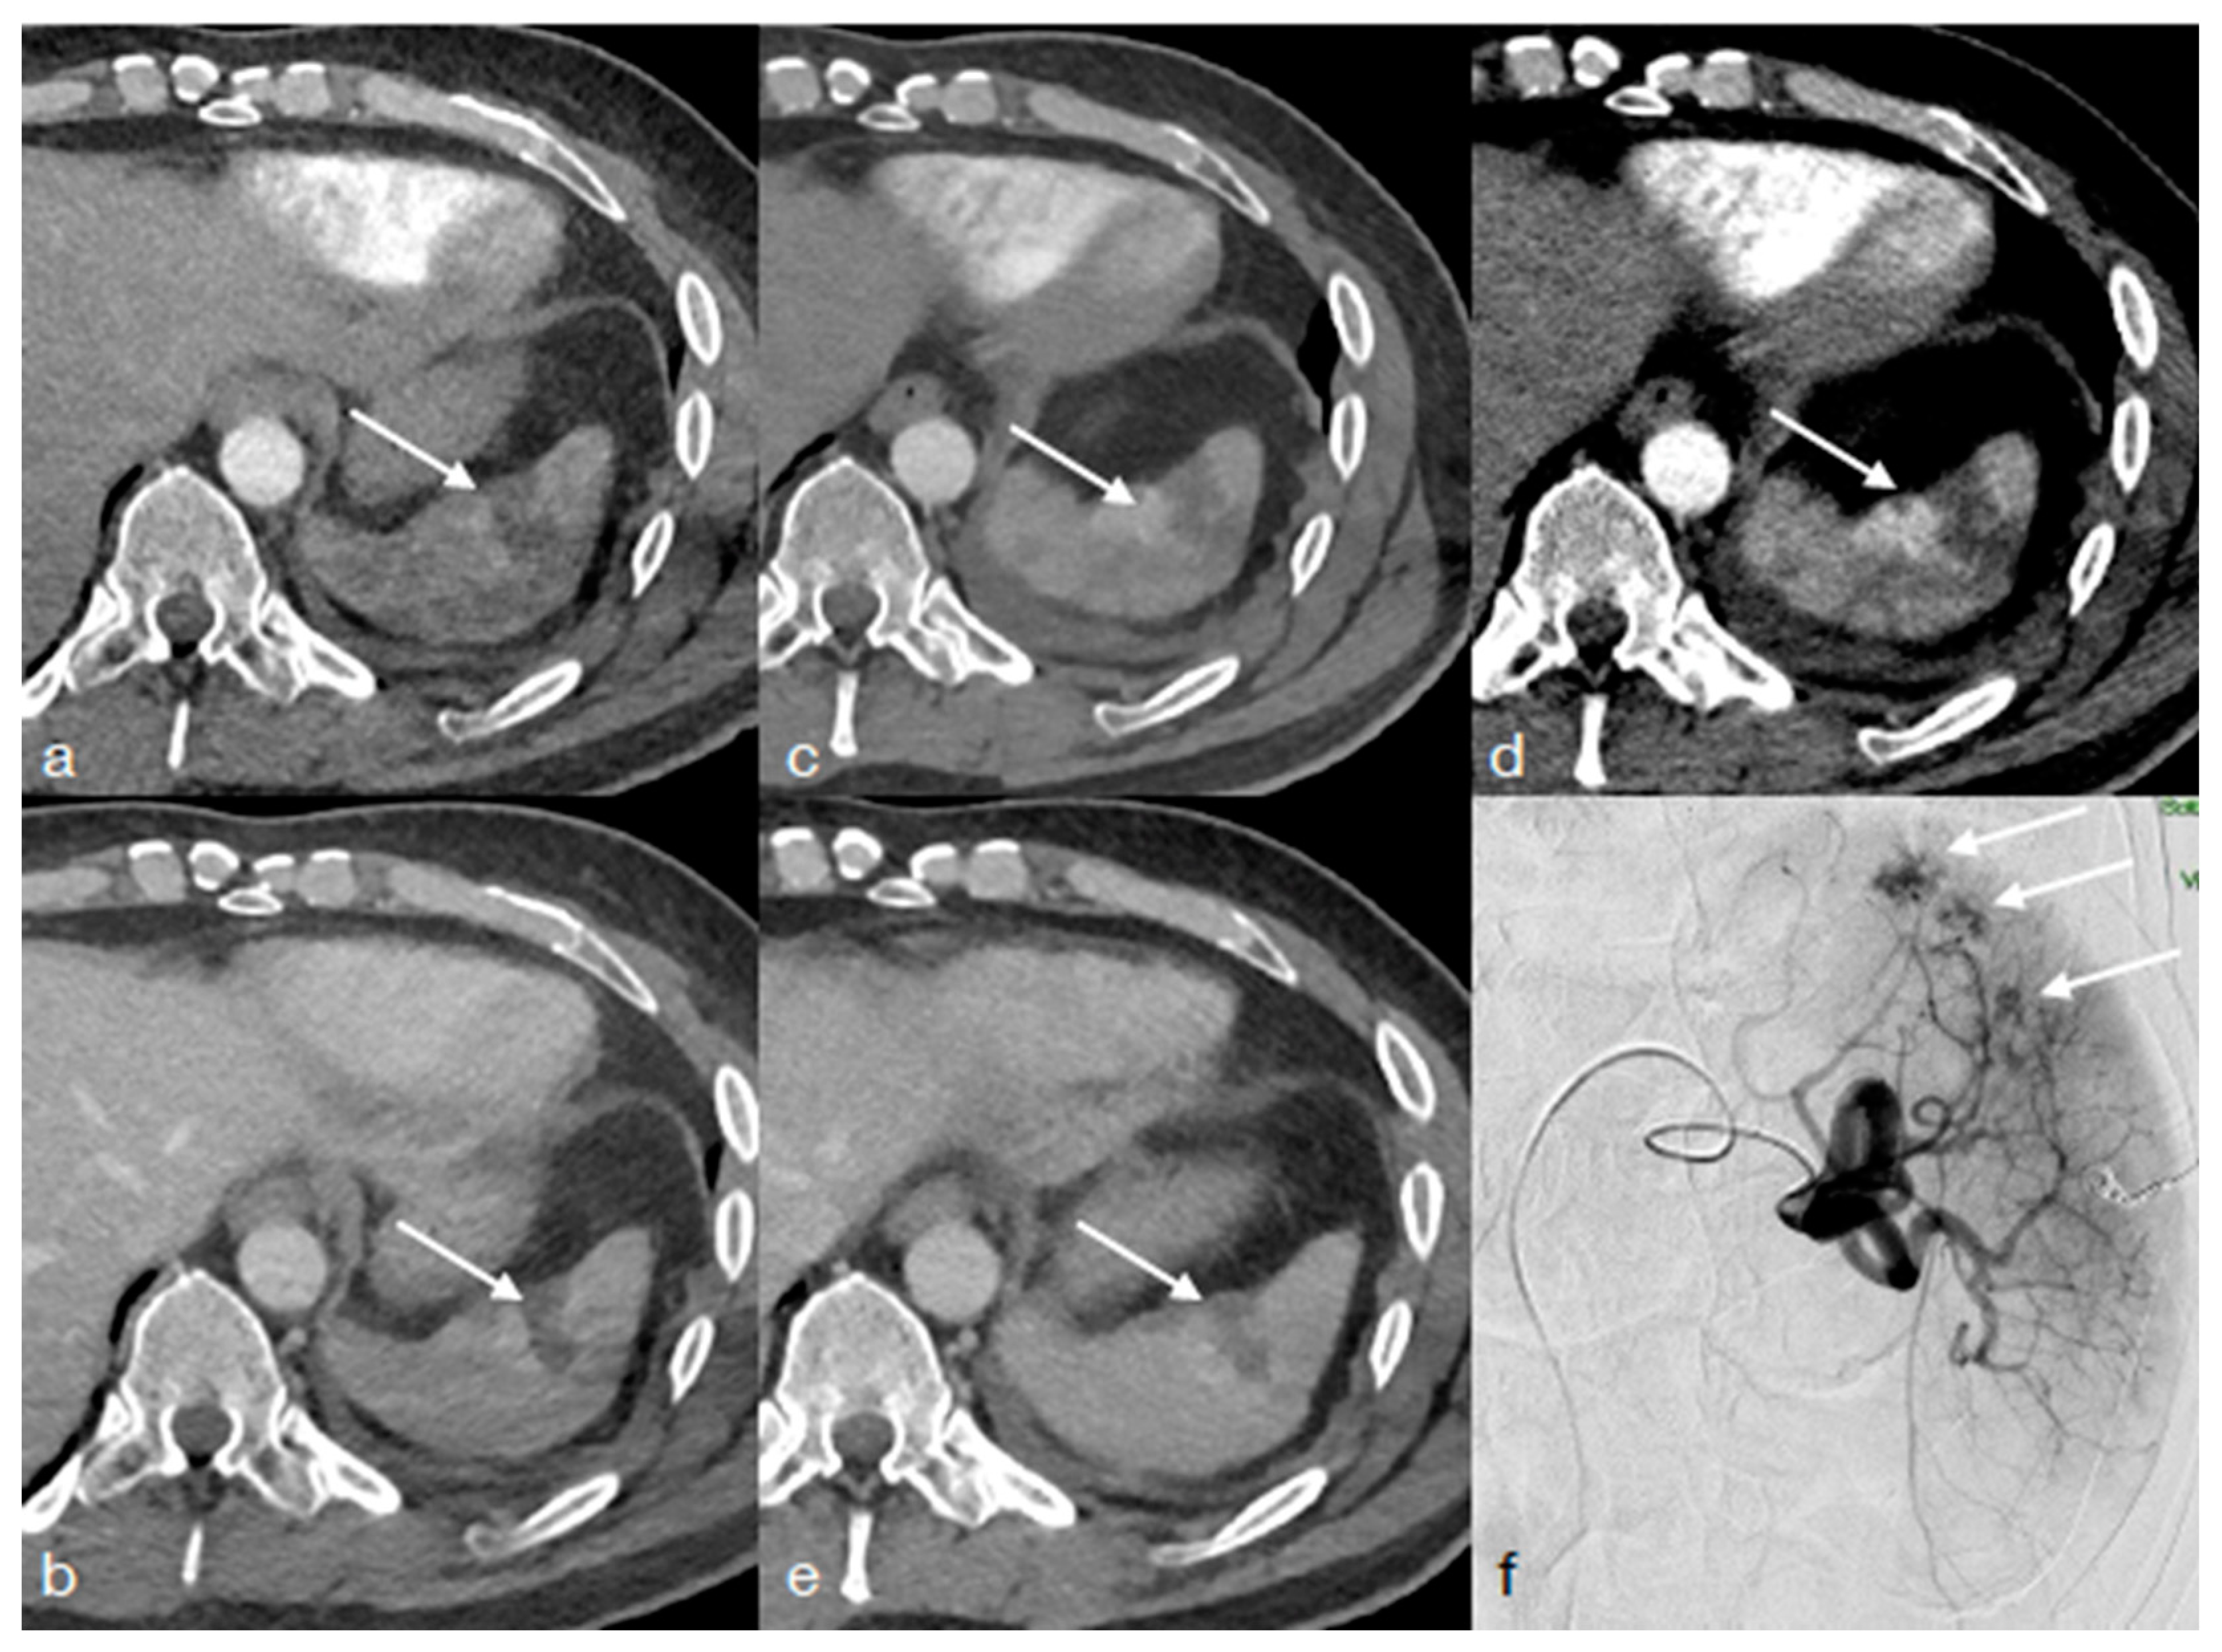

- Scaglione, M.; Pinto, A.; Pinto, F.; Romano, L.; Ragozzino, A.; Grassi, R. Role of contrast-enhanced helical CT in the evaluation of acute thoracic aortic injuries after blunt chest trauma. Eur. Radiol. 2001, 11, 2444–2448. [Google Scholar] [CrossRef]

- Iacobellis, F.; Iacobellis, F.; Scaglione, M.; Scaglione, M.; Brillantino, A.; Brillantino, A.; Scuderi, M.G.; Scuderi, M.G.; Giurazza, F.; Giurazza, F.; et al. The additional value of the arterial phase in the CT assessment of liver vascular injuries after high-energy blunt trauma. Emerg. Radiol. 2019, 26, 647–654. [Google Scholar] [CrossRef]